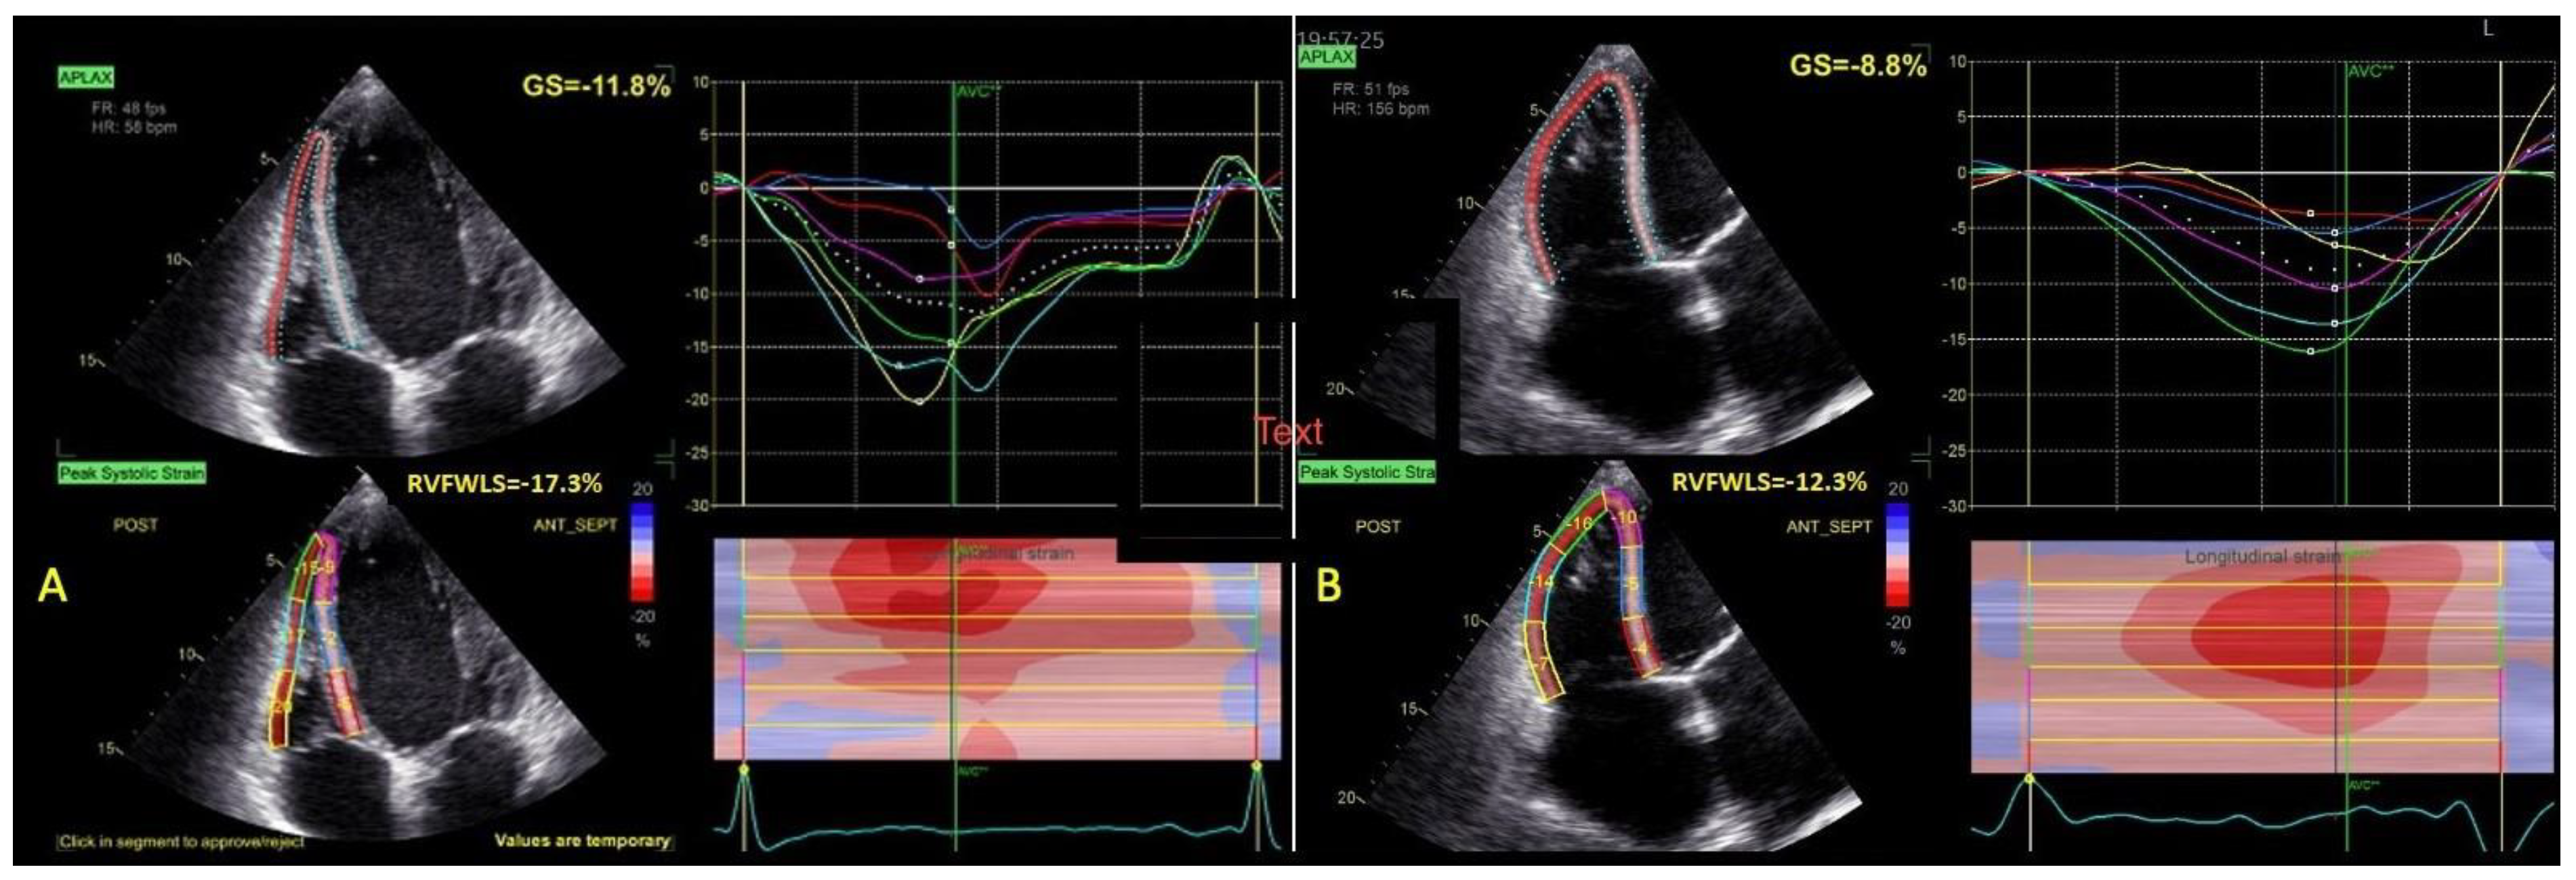

| RVFWLS (%) | 17.2 ± 7 | 13.2 ± 5 | 0.004 |